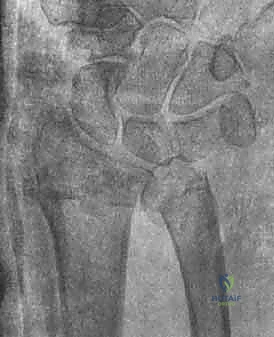

2. كسور رأس الزند (Ulnar Head Fractures)

رأس الزند هو الجزء المفصلي الدائري الذي يدور حوله الكعبرة.

* كسور مفصلية (Articular Fractures): تمتد خطوط الكسر لتشمل الغضروف المفصلي. إذا لم يتم إعادة العظام إلى وضعها التشريحي المثالي (Anatomic Reduction)، فإن المريض سيكون عرضة للإصابة بخشونة المفاصل المبكرة (Post-traumatic Osteoarthritis) وفقدان القدرة على تدوير الساعد.

* كسور غير مفصلية: تقع تحت السطح المفصلي مباشرة، ولكنها قد تؤدي إلى تشوه في زاوية رأس الزند.

صورة لكسر في رأس الزند

استخدام الأشعة السينية في التشخيص

1. الأشعة السينية (X-rays): بوضعيات متعددة (أمامية خلفية، وجانبية دقيقة). الوضعية الجانبية الحقيقية (True Lateral) حاسمة لاكتشاف أي خلع جزئي في المفصل (DRUJ).

2. الأشعة المقطعية ثلاثية الأبعاد (3D CT Scan): تُستخدم في الكسور المفتتة أو كسور رأس الزند المفصلية المعقدة، حيث تعطي خريطة دقيقة للجراح قبل الدخول لغرفة العمليات.